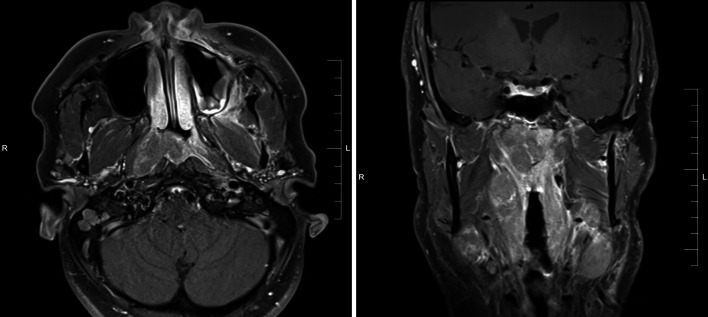

The patient was a 40-year-old male never-smoker who presented with right ear fullness, epistaxis, and bilateral cervical and supraclavicular lymphadenopathy. His past medical history included tonsillectomy and adenoidectomy at age 20, as well as tuberous sclerosis (TSC). Nasopharyngoscopy identified a right-sided mass involving the roof and lateral wall of the nasopharynx and magnetic resonance imaging (MRI) confirmed the presence of a 3.7 cm × 2.9 cm nasopharyngeal mass which extended into the oropharynx and expanded the fossa of Rosenmuller, but did not involve the nasal cavity (Fig. 1). Staging studies including computed tomography (CT) and fluorodeoxyglucose positron emission tomography (FDG-PET) demonstrated bilateral enlargement of level II through V lymph nodes in the neck but no evidence of distant metastatic disease.

Fig. 1.

Magnetic resonance imaging (MRI) demonstrate the presence of a 3.7 cm x 2.9 cm mass arising in the nasopharynx extending into the oropharynx. No involvement of the nasal cavity was identified